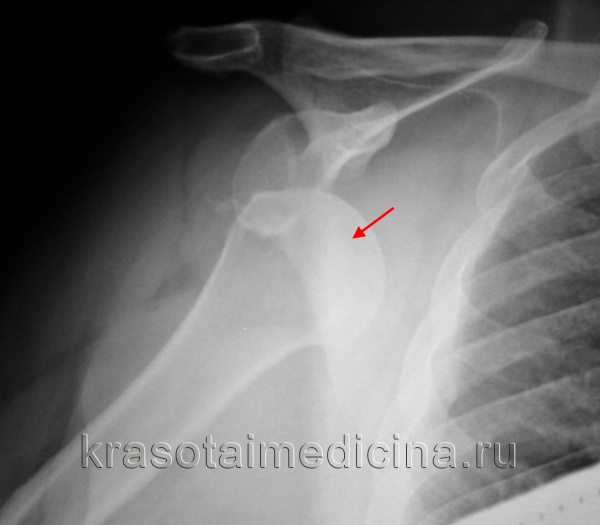

Рентгенограмма: перелом шейки лопатки (красная линия) и основания акромиального отростка (зеленая линия).